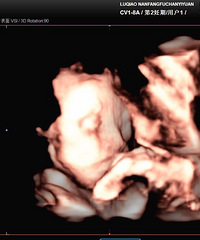

预产期:2022.08.30建卡医院:台州妇女儿童医院产检医院:台州妇女儿童医院胎宝宝小名:未定生产医院:台州妇女儿童医院B超照片/孕期相关照片一张:

预产期:2022年4月10日建卡医院:椒江妇幼保健所产检医院:椒江妇幼保健所胎宝宝小名:崽生产医院:台州妇女儿童医院或路桥恩泽医院B超照片/孕期相关照

预产期:2022/2/20建卡医院:路桥路北卫生院产检医院:椒江妇幼保健所胎宝宝小名:肉肉生产医院:考虑妇女儿童医院,台州市中心医院,第一张B超照片:

预产期:2021.11.8建卡医院:台州妇女儿童医院产检医院:台州妇女儿童医院胎宝宝小名:未起生产医院:台州妇女儿童医院B超照片/孕期相关照片一张:

预产期:2021.2.13建卡医院:台州医院产检医院:台州医院胎宝宝小名:由由/小丸子/绵绵/boly生产医院:看情况吧B超照片/孕期相关照片一张:

预产期:2021年4月19日(提前3月10日生)建卡医院:桐屿卫生院产检医院:恩泽宝宝小名:牛小壮生产医院:恩泽B超照片/孕期相关照片一张:

预产期:2022.2.4建卡医院:临海邵家渡卫生院产检医院:恩泽妇产+临海妇幼保健院胎宝宝小名:lucky生产医院:预计台州医院新院B超照片/孕期相关照片一